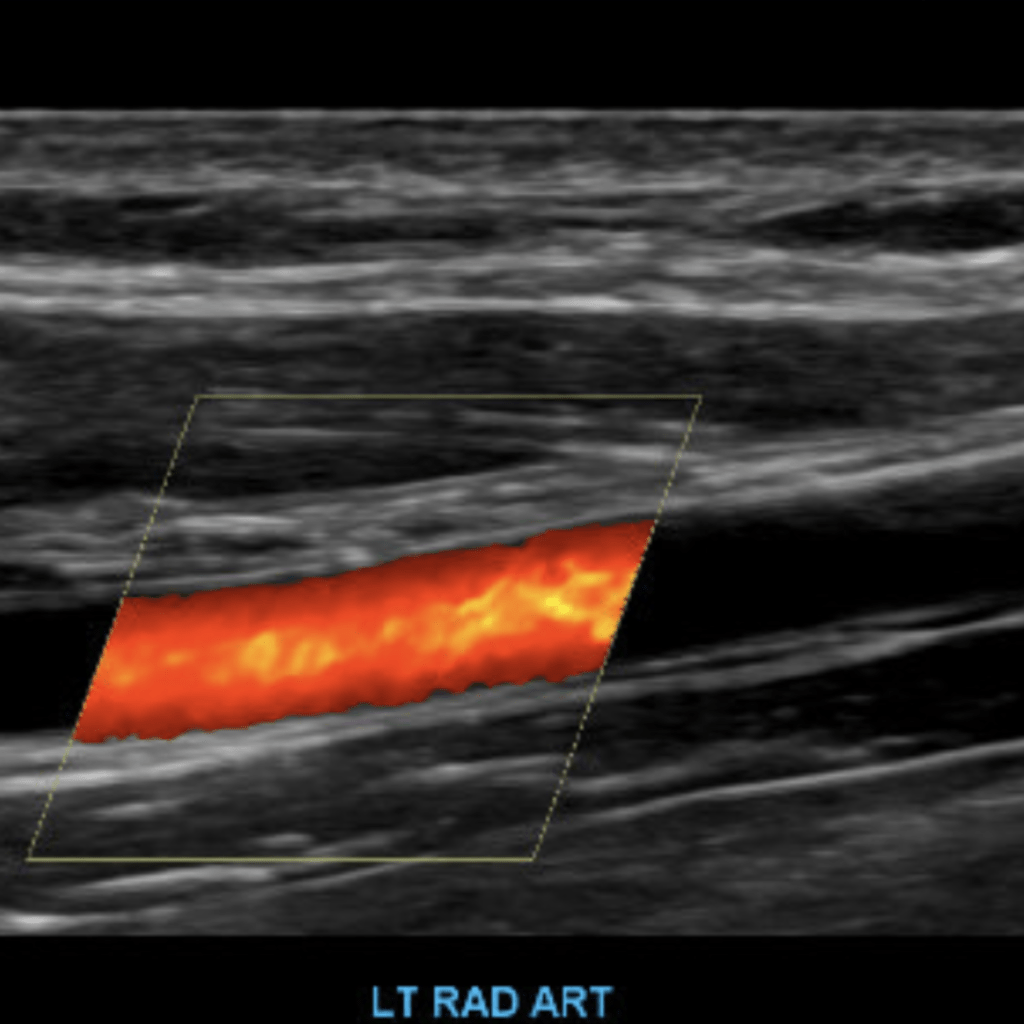

The subclavian artery arises from the brachiocephalic artery on the right and off of the aortic arch on the left. This artery further divides into the axillary, brachial, radial, ulnar, palmar and digital arteries respectively.